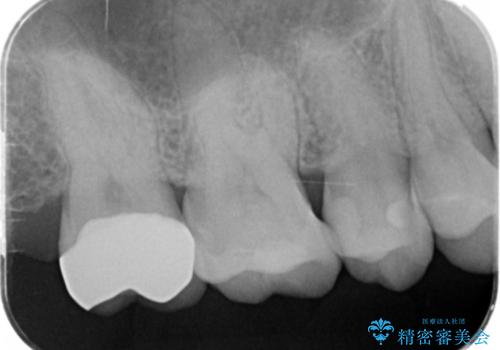

- 口の中に見える銀歯を、金属アレルギーの対策と審美性の向上のため全て除去したい!と希望され来院されました。

銀歯を丁寧に除去したのち、精度の良いセラミックインレー、セラミッククラウンで修復・補綴処置を行っていきます。

- 62.7万円(ジルコニアクラウン×3・仮歯×3・セラミックインレー×3)費用は治療当時の料金となります